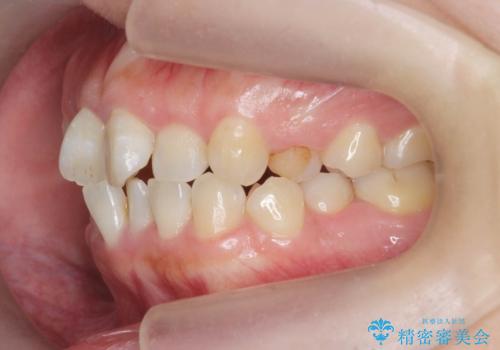

- 前歯のねじれを改善したい、と矯正治療を希望され来院されました。

上下の歯のがたつきを改善するマウスピース矯正治療と、下顎に見られる大きな骨隆起を外科的に除去する治療計画を進めていきます。